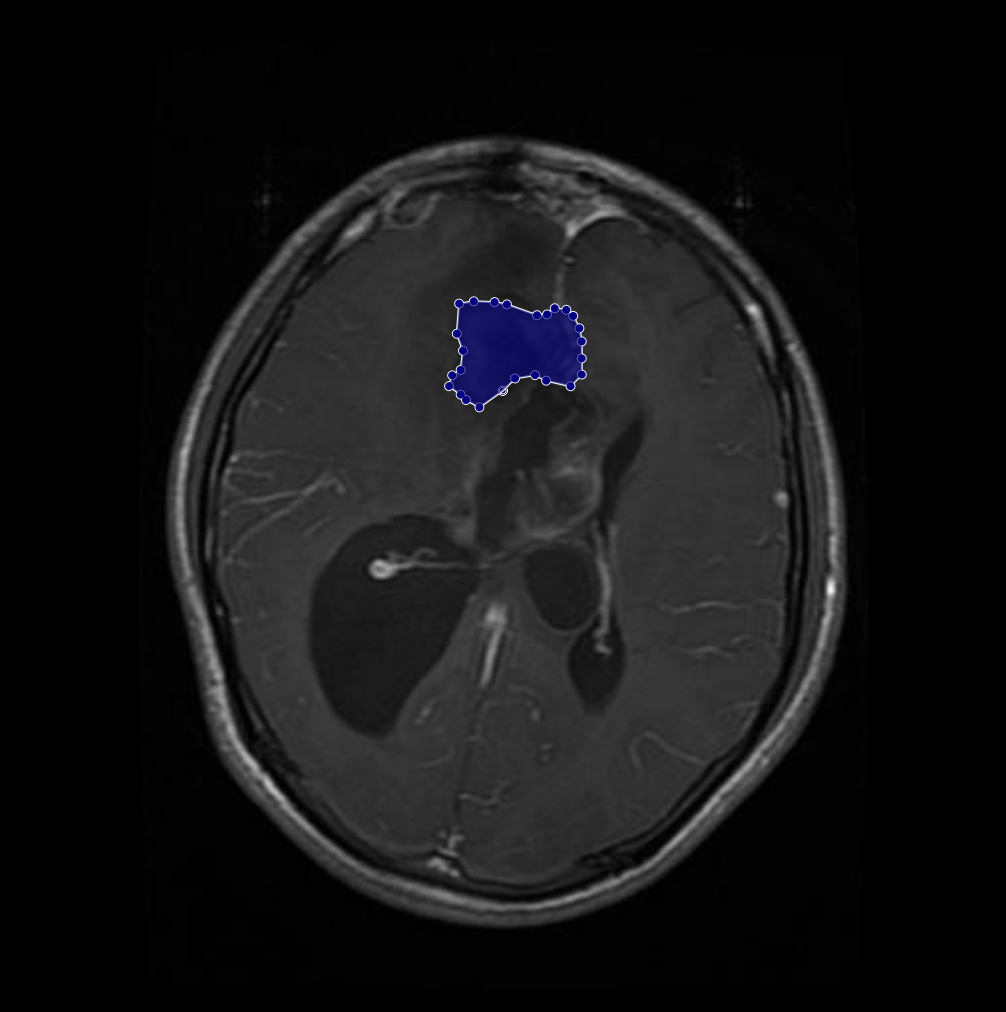

Figure 2: Samples of Meningioma segmentation across different imaging planes

Meningioma: Meningiomas arise from the meninges and are generally well‑circumscribed and homogeneous, making them easier to segment. However, their location adjacent to critical structures such as dural sinuses and cranial nerves can complicate diagnostic tasks. An example of a meningioma and its segmentation mask is presented in Figure 2, illustrating the clarity of its boundaries.